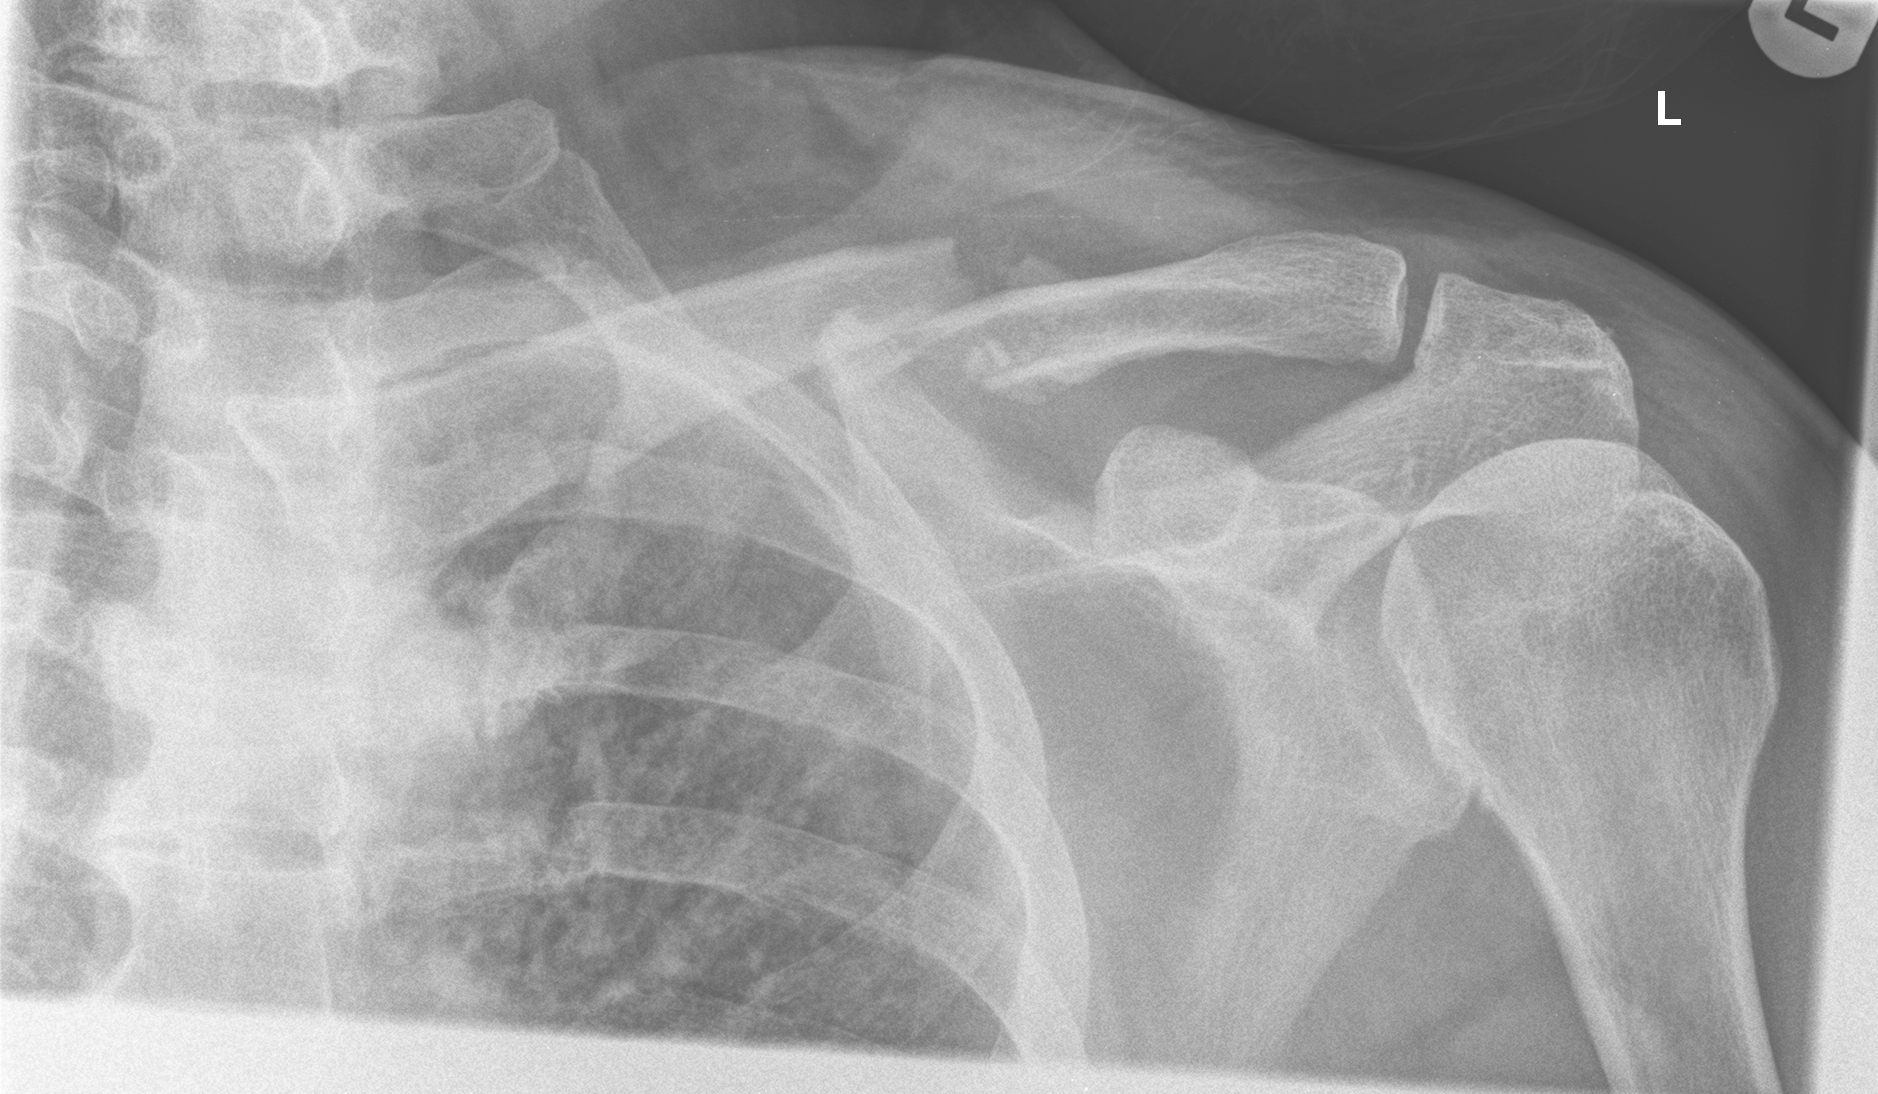

2. Left panel: right femoral head fracture and sclerotic metastasis of the pubic bone. On previous CT no metastasis was found in the femoral bone. Right panel: Fracture of the left clavicle in a man after falling off the bike.